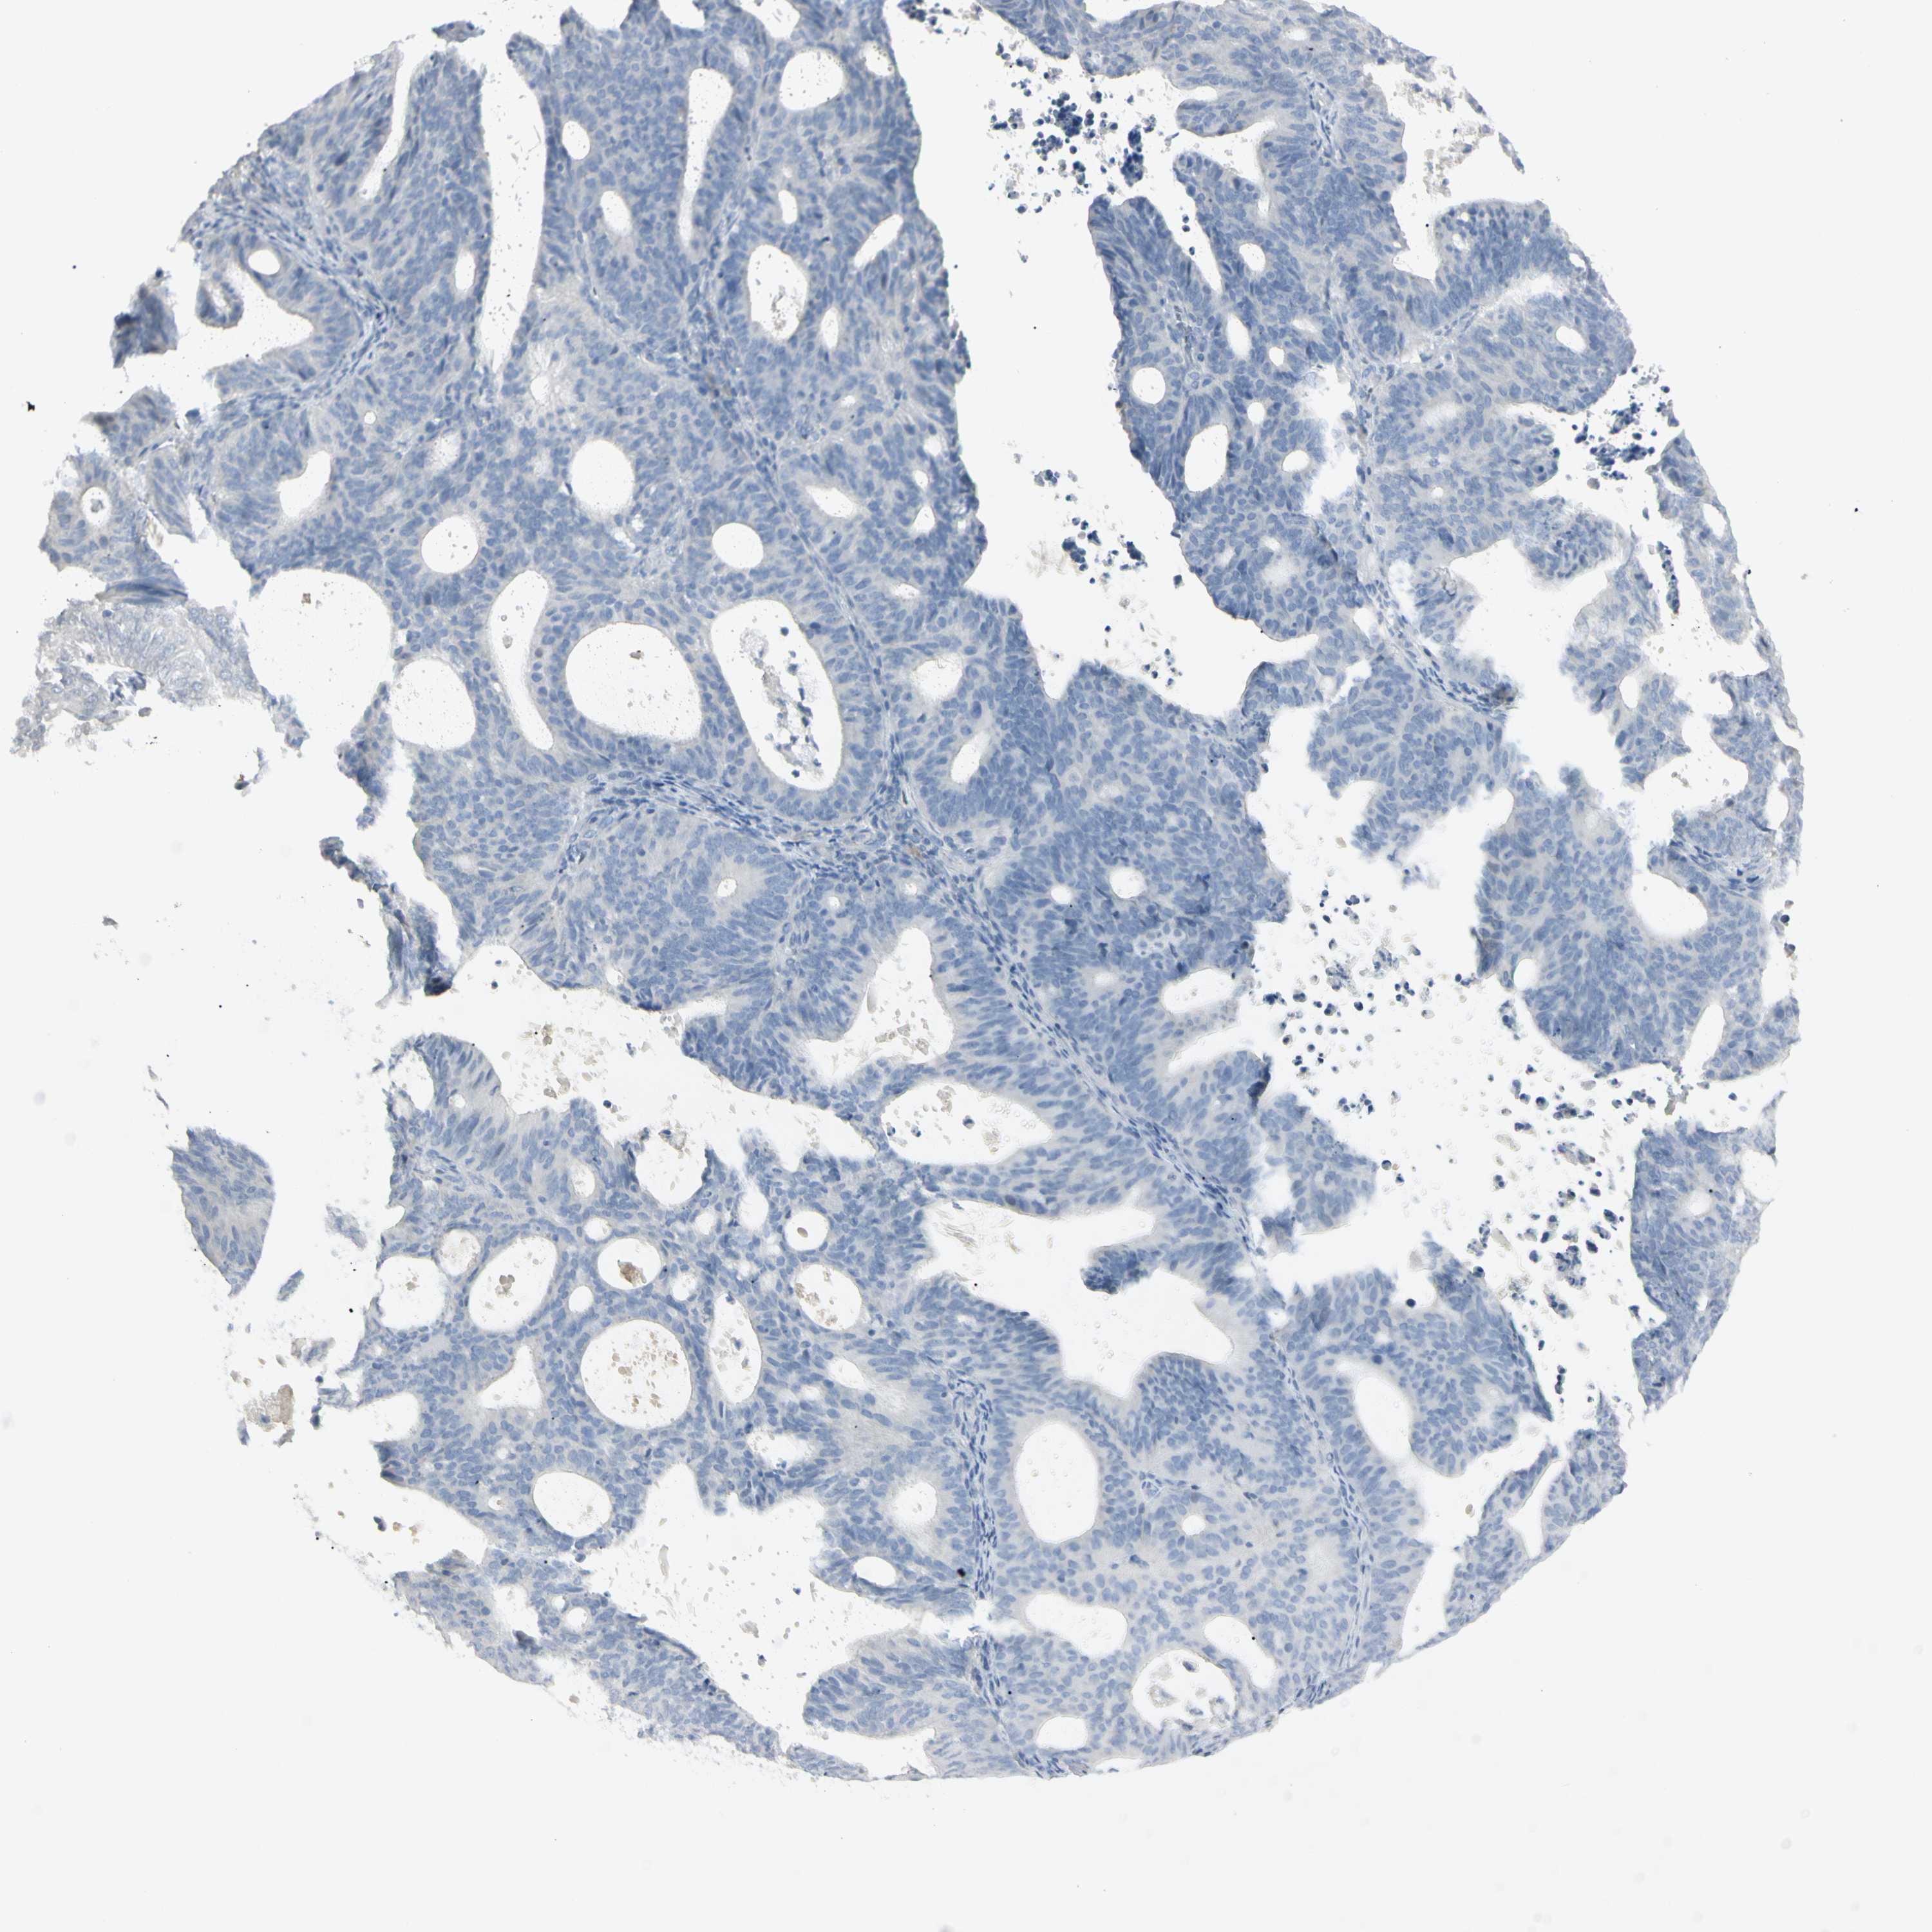

ENDOMETRIAL CANCER - Protein expressioni

A mouse-over function shows sample information and annotation data. Click on an image to view it in a full screen mode. Samples can be filtered based on level of antibody staining by selecting one or several of the following categories: high, medium, low and not detected. The assay and annotation is described here.

Note that samples used for immunohistochemistry by the Human Protein Atlas do not correspond to samples in the TCGA dataset.

Antibody stainingi

Antibody staining in the annotated cell types in the current human tissue is reported as not detected, low, medium, or high, based on conventional immunohistochemistry profiling in selected tissues. This score is based on the combination of the staining intensity and fraction of stained cells.

Each image is clickable and will lead to virtual microscopy that enables deeper exploration of all samples and also displays staining intensity scores, fraction scores and subcellular localization as well as patient and tissue information for each sample.

Antibody HPA009177

Antibody CAB002661

Staining

High

Medium

Low

Not detected

Intensity

Strong

Moderate

Weak

Negative

Quantity

>75%

75%-25%

<25%

None

Location

Nuclear

Cytoplasmic/membranous

Cytoplasmic/membranous,nuclear

Adenocarcinoma, NOS

Neoplasm, malignant, NOS